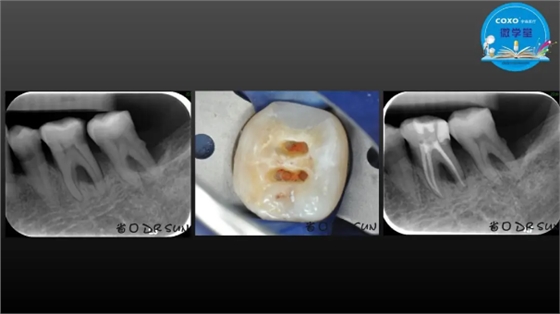

主讲:孙书昱

主任医师,牙体牙髓副主任, 广东省口腔医院牙体牙髓科 主任医师。2003年硕士研究生毕业,研究方向为牙体牙髓病学,擅长于牙体牙髓病的诊断、龋齿、牙髓炎、根尖周病的治疗以及前牙美容修复。